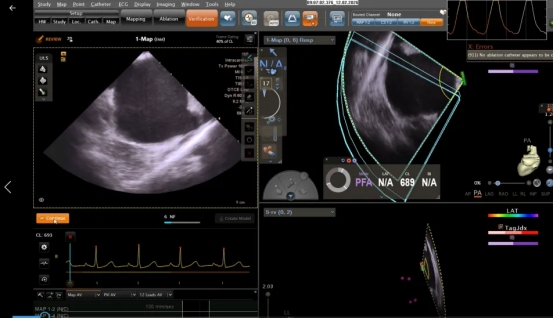

这个手术的特别之处在于,借助CARTOSOUND™ FAM模块,基于深度学习(DL)算法,三维心腔内超声导管构建实时、高效的左房的模型,实施VARIPULSE 脉冲消融导管术。简单说,CartoSound Fam 4D超声建模就像给心脏做了一个“3D立体扫描”,依托人工智能深度学习算法,通过一根细小的超声导管在心脏内旋转,就能自动构建出左心房的精准模型,相当于给医生提供了“实时导航”,能清晰看到心脏的每一个细微结构,为手术的安全性与规范化实施提供了重要保障。

第二步:构建心脏3D模型。借助CARTOSOUND™ FAM模块基于深度学习(DL)算法,通过在右心房旋转三维心腔内超声导管,自动构建左心房精准模型,为后续操作提供清晰的“导航地图”。ICE导管在手术过程中为术前血栓筛查、左心房解剖结构识别、导管定位及关键操作指导提供了实时、清晰的影像支持。既高效,又精准。